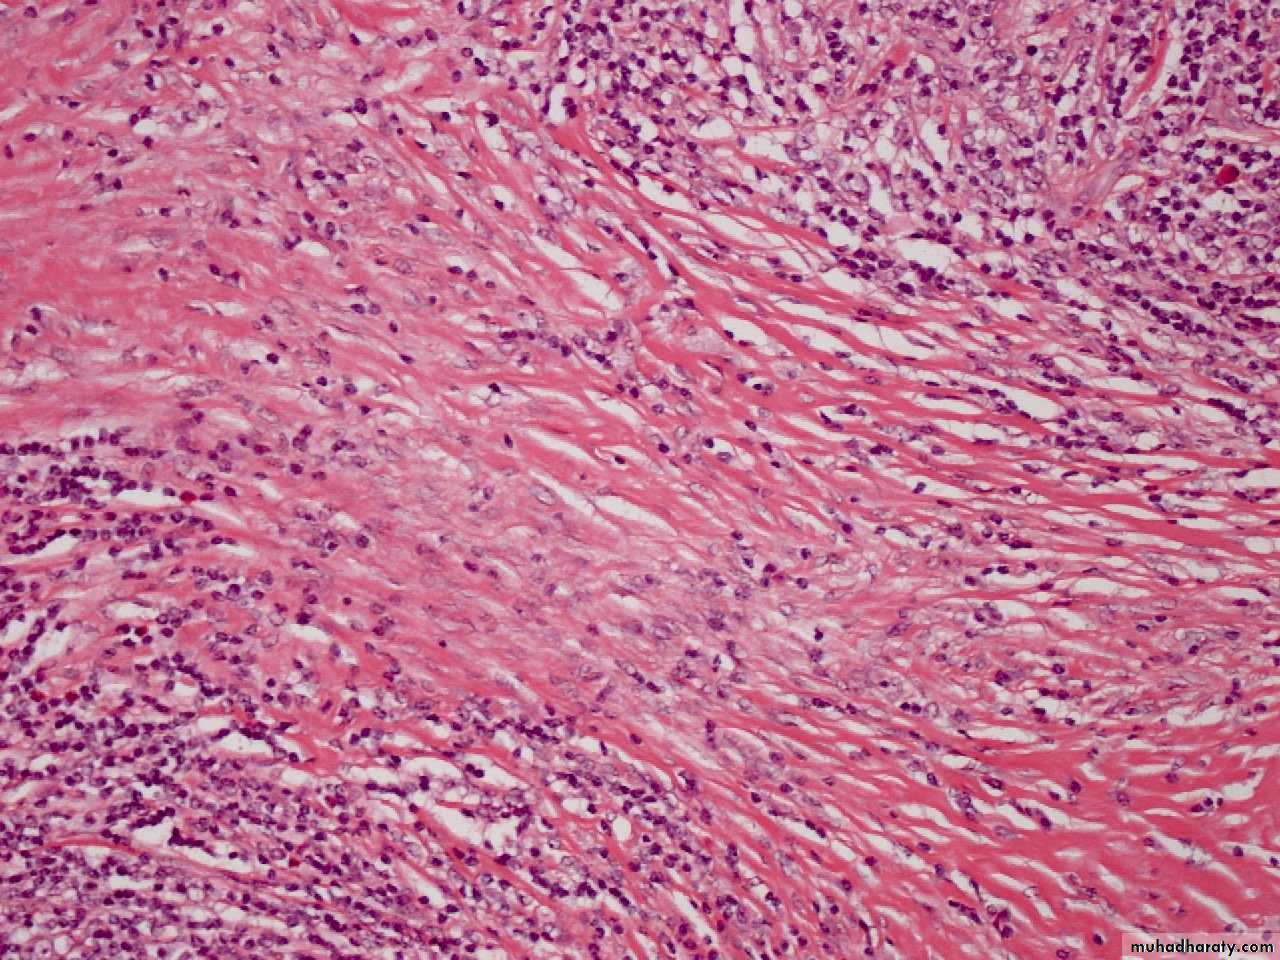

Nodular sclerosing HL

• Characterized by fibrotic capsule and bands subdividing tissue and

• Lacunar variant Reed Sternberg cell

NSCHD

M. 39Y. PARA AORTIC, MESENTRIC LYMPHADEOPATHY,ANAEMIA,LETHARGY, NODE BIOPSYHodgkin's disease, nodular sclerosis type, lacunar cell HP mic

large cells with a surrounding prominent clear space, an artefact of formalin fixation. These are the lacunar cells characteristic for the nodular sclerosis type of Hodgkin's disease.M. 39Y. PARA AORTIC, MESENTRIC LYMPHADEOPATHY,ANAEMIA,LETHARGY, NODE BIOPSY